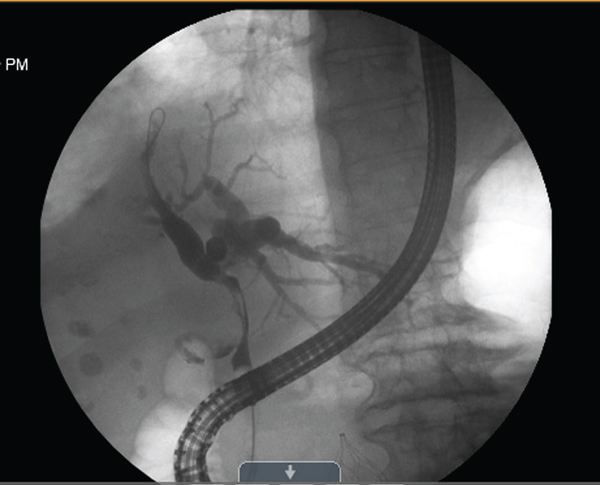

Upon arrival at our hospital, the patient underwent an endoscopic retrograde cholangiopancreatography (ERCP) with the removal of small stones in the common bile duct, sphincterotomy, and two stent placements with ends terminating in the distal right and left hepatic ducts. However, despite this, there was still tapering in the common hepatic and common bile ducts noted from extrinsic compression from the large stones in the gallbladder and a significant filling defect through the cystic duct (Figure 1). Additionally, the patient developed a fever and leukocytosis and persistently elevated bilirubin, with the most likely cause being an obstruction of the biliary stents causing persistent cholangitis and cholecystitis. The ERCP was repeated, and a third stent was placed. The patient’s fever was controlled, and the bilirubin began to trend down.